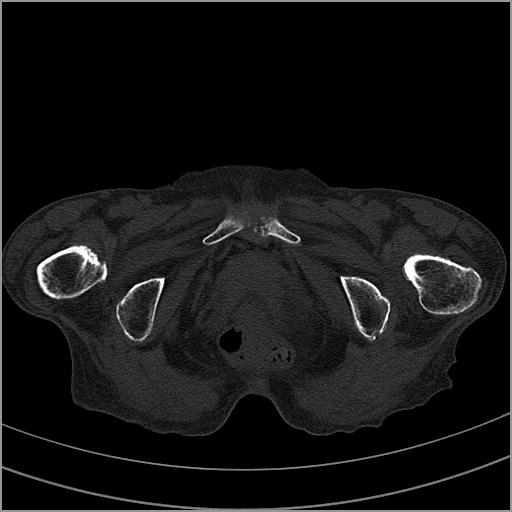

以下是引用老爱克斯新网客在2009-2-3 19:42:00的发言:[br]右侧髋臼及右侧股骨头可见明显骨质破坏,以溶骨性破坏为主,无明显硬化,髋关节间隙变窄,周围软组织明显肿胀,密度不均,脂肪间隙消失。[br] 诊断:右侧髋关节感染性病变,右侧髋关节结核的可能大。[br] 鉴别诊断:1.股骨头缺血坏死,单纯股骨头缺血坏死病例不会累积髋臼骨破坏。2。退行性关节炎,以骨质增生为主,伴有关节面硬化,骨质破坏呈多发小囊状破坏为主,其周围可见硬化环。3.股骨头缺血坏死晚期(第四期)骨质破坏可伴髋关节退行性变,可有骨质增生,但此时骨破坏以股骨头破坏为主,不应该伴有髋臼骨质破坏,因为股骨头的骨破坏是因血运中断,而没有髋臼的血运中断,又没有细菌的感染,怎么能造成髋臼的骨破坏呢。